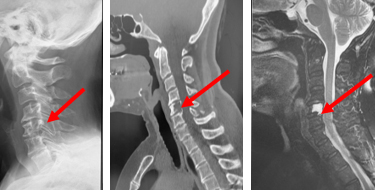

体幹の柔軟性が失われたり、転倒により骨折を生じやすくなります。非常に不安定性が強い骨折となったり、軽微な転倒の数ヶ月後に神経障害を生じたりすることがあるので注意が必要です。

脊椎や靭帯などの骨化の程度や骨折の有無を判断するために、X線検査やCT検査、MRI検査を行う場合があります。骨折の有無は、X線検査のみでは診断が難しいことも少なくありません。また、生活習慣病との関連が指摘されているため、手足の血流や動脈硬化の有無を評価するため、両手足の血圧を測ったり、骨脆弱性を評価するために骨密度検査を行うことがあります。

生活習慣病との関連が指摘されているため、減量や糖尿病のコントロールをお勧めします。骨折を生じた場合には、コルセットによる装具治療で骨癒合(骨がくっつく)が得られることもありますが、放置した場合に偽関節(骨がくっつかない)や将来的な神経障害を生じやすいため、不安定性が強い場合などには、手術治療を考慮します。手術では一般に固定術が必要となります。当センターでは、適応をよく検討した上で、なるべく負担の少ない手術法を取り入れています。